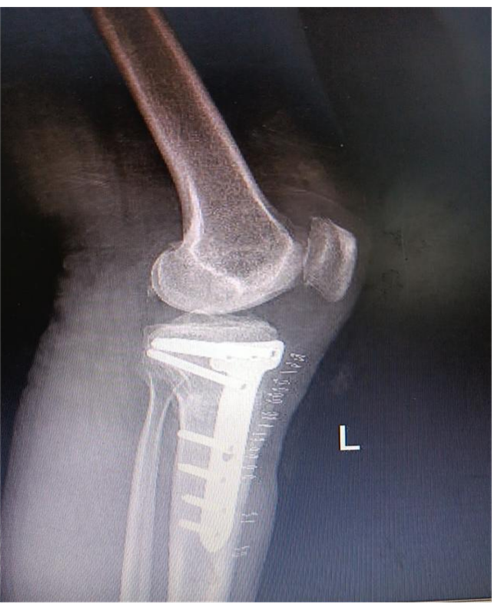

手术如期进行,在骨科手术机器人“透视眼”和“稳定手”的精准操作下,患者术中测量内翻畸形纠正,胫骨近端后倾角92°。术后,患者左膝疼痛明显缓解,关节活动度较术前明显改善,术后3天即扶拐下地行走,4周后即可完全负重。